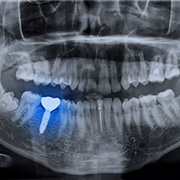

What Are Dental Implants?

Dental implants are a comprehensive approach to tooth restoration that does what no other solution can: replicate a tooth from root to crown.

Rather than simply giving you a fake tooth that sits on top of your gums, dental implants are held firmly in place using a small titanium post that is surgically inserted into your jaw that will naturally bond with the surrounding bone. Not only does this give it the security of a natural tooth, but it also ensures the long-term health of your gums and jaw.